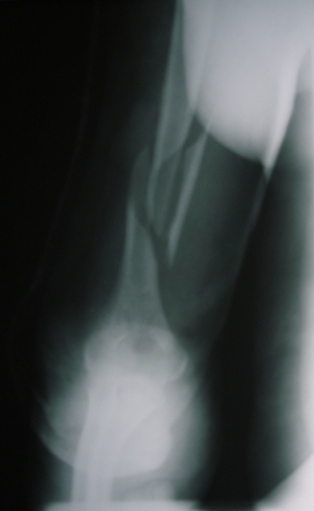

что  не  получилось  и  берем  на  операцию. Теперь непосредственно по

больному.   Лечим   функциональной   повязкой,   добились   вот   чего

(приложение).  Будем  признательны  за  дальнейший  комментарий  - мое

мнение, что можно продолжить без операции.

Имя     : Прямой.JPG

Тип     : image/jpeg

Размер  : 43447 байтов

Описание: отсутствует

Url     : http://weborto.net:8080/pipermail/ortho/attachments/20100223/f10e997d/attachment-0006.jpeg